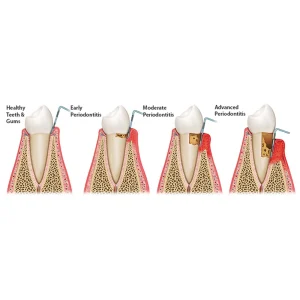

The GDC Marking Probe-3 (Pow6) is a versatile periodontal instrument designed for precise assessment of pocket depths and dental health. Its long, thin, blunted tip is inscribed with accurate millimeter markings (1-2-3-5-7-8-9-10) for easy readability. This probe helps evaluate the periodontium’s condition effectively. Additionally, its sharp-pointed sickle probe enhances tactile sensitivity, allowing dentists to detect tooth decay and surface irregularities on enamel. Made from durable materials, the probe is built for long-term use, ensuring accuracy and comfort during dental examinations. An essential tool for professional dental practices, it aids in diagnosing and planning effective periodontal treatments.